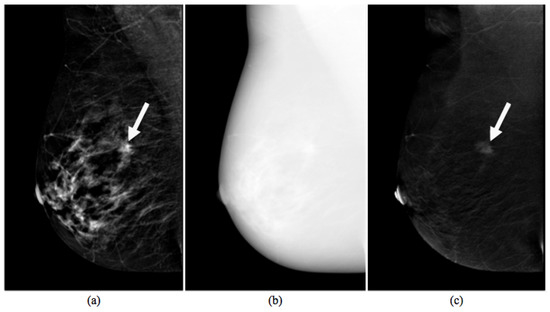

2.1.1. CESM Examination